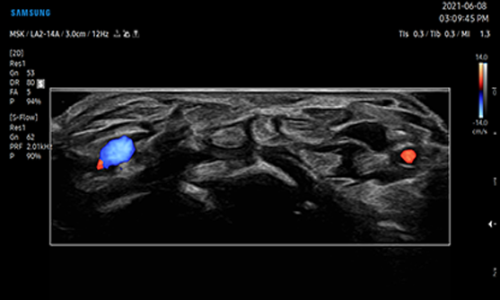

Nel caso in cui si preveda l’aggiunta del Doppler, si ha l’opportunità di valutare la vascolarizzazione di masse eventualmente presenti e di ottenere informazioni a proposito della circolazione nei vasi.

La rappresentazione sul monitor dell’effetto Doppler può avvenire tramite segnali sonori e grafici, o in alternativa attraverso il color Doppler, che consiste in un effetto colore dentro ai vasi.

S-Flow™ è una tecnologia di imaging Power Doppler direzionale, contribuisce a rilevare anche i vasi sanguigni periferici. Consente di effettuare diagnosi accurate quando l’esame dei flussi ematici risulta particolarmente complesso.